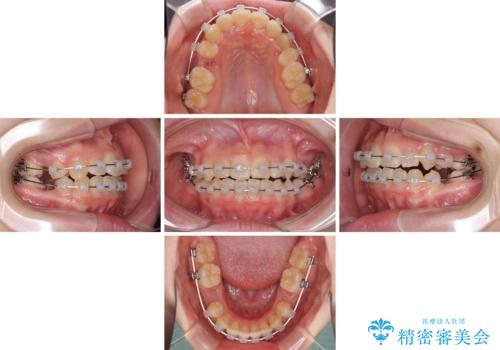

乳歯が残っている 目立たない装置での抜歯矯正

- クリアブラケット

- 八重歯と乳歯が残っていることを気にして来院された患者様です。

乳歯が3歯残っており、下顎は左右ともに後続永久歯がない状態でした。

口元が突出しており、口が閉じにくかったため、乳歯を含め上下5歯を抜歯して矯正治療を行うこととしました。

下顎の乳歯は永久歯と比べて幅が大きいため、抜歯した場合のスペースが大きく、治療には長期間を要することが一般的です。

今回の患者様は中学生ということもあり、成人の患者様と比べ動きが速く、2年間で治療を終えることができました。